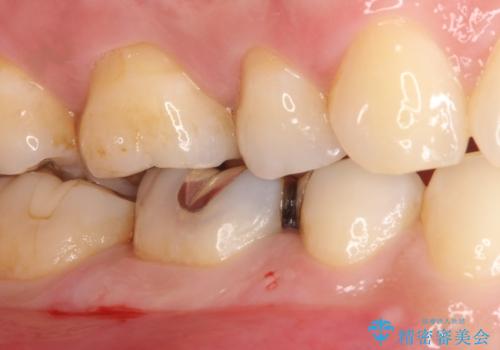

- メタルインレーによる審美障害を主訴に来院されました。

セラミックインレーに治療を行っております。

e-max プレスインレーにて修復治療を行っているため適合性及び審美性の高い治療を行うことができます。